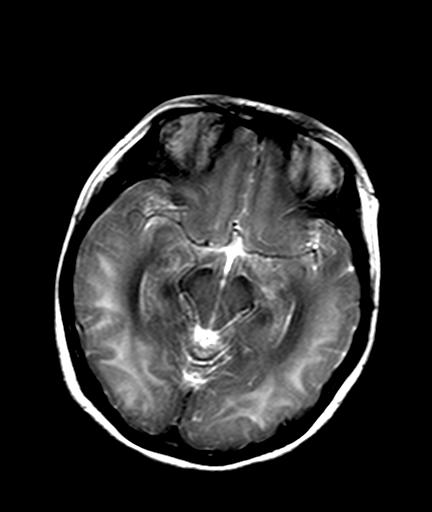

发热、头痛伴精神异常1周

较对称性脑白质异常信号,深部白质t2明显低信号(铁质沉积过多?)

考虑脑白质病变,请结合临床病史及实验室检查进一步分析。

f 23岁